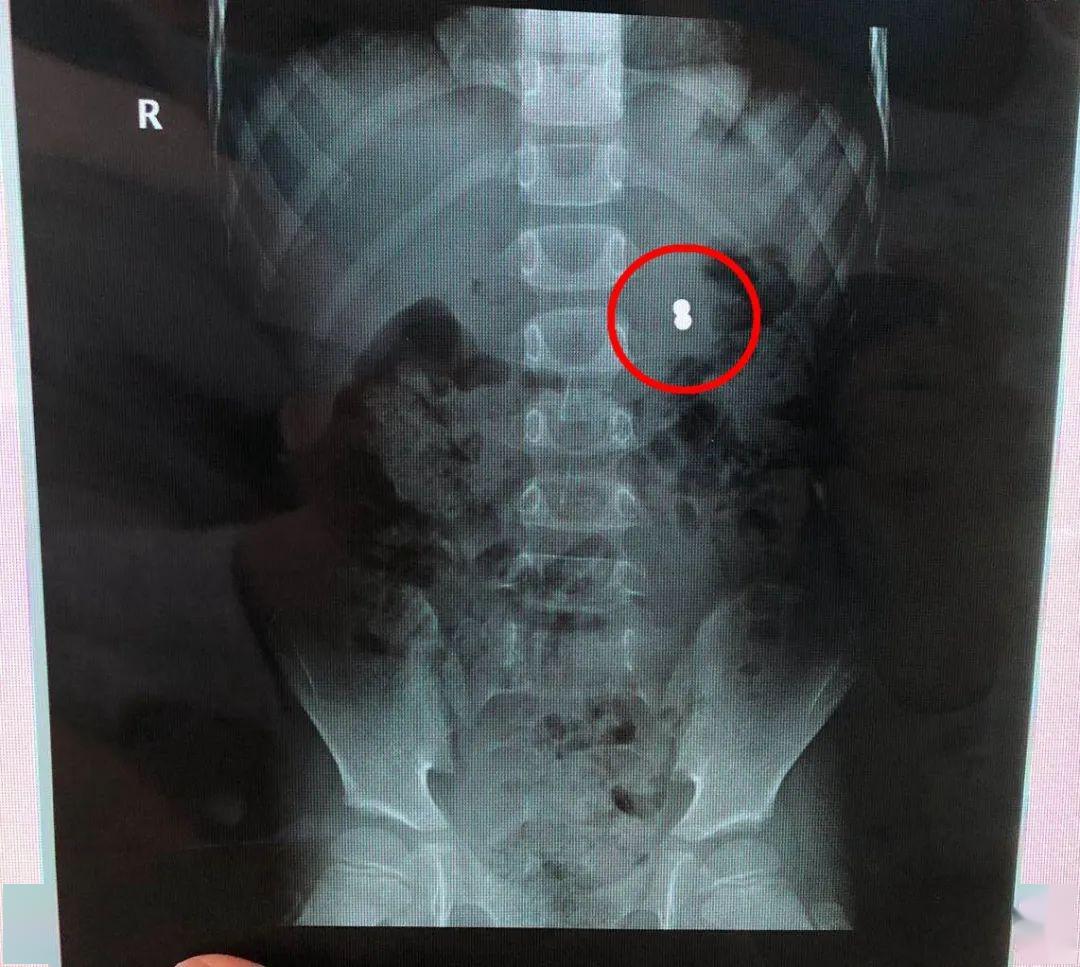

当地医院腹部CT提示:两个并列的磁力珠位于胃内 。 但由于当时豪豪的消化道症状很快消失了 , 父母也就没有在意 。

父母带着豪豪再次到医院检查 , 腹部立位片见左上腹异物 , 胃镜下发现只有一枚磁珠嵌顿于胃体大弯皱褶处 , 另一枚相邻的磁珠可能已经穿透胃壁进入腹腔 , 加之周围粘膜充血、糜烂、水肿 。

文章图片

B超提示:两颗直径均为5mm的磁力珠相邻排列 , 一颗磁珠在胃壁粘膜层肌层嵌顿 , 另一颗磁珠已穿破了浆膜层 , 且浆膜层已粘连包裹显示不清 , 周围大网膜水肿、粘连 。

通过手术抓取 ,两颗磁力珠被顺利取出 。